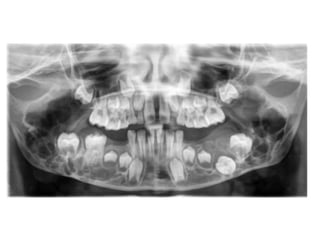

Ameloblastoma

13